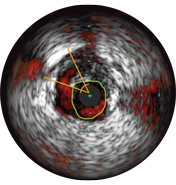

Диаметры сосудов можно определять в проксимальных и дистальных контрольных точках за счет значений диаметров просветов, средних диаметров стенок (в центральной точке между просветом и сосудом) или диаметров сосудов.

ВСУЗИ помогает более точно определить степень и тип стеноза (т.е. минимальную площадь просвета (MLA), объем бляшки и кальций). Несмотря на то что ВСУЗИ позволяет выявить разрыв бляшки, наличие тромбов и диссекции, кальций наиболее распространен при рутинных ЧКВ. Оказывая большее влияние на стратегию стентирования, кальций отображается в виде очень ярких участков с акустическим затенением, которое блокирует изображение сзади. Также могут наблюдаться реверберации.

Существует статистика, что частота возникновения краевых диссекций после имплантации стента с лекарственным покрытием составляет 10%, при этом практически 40% из них не выявляются при ангиографии. Угол диссекции ≥ 60° или MLA <4 мм2 указывают на высокую степень диссекции, требующую лечения. Такие характеристики связаны с более высокой частотой возникновения раннего тромбоза стента 2.